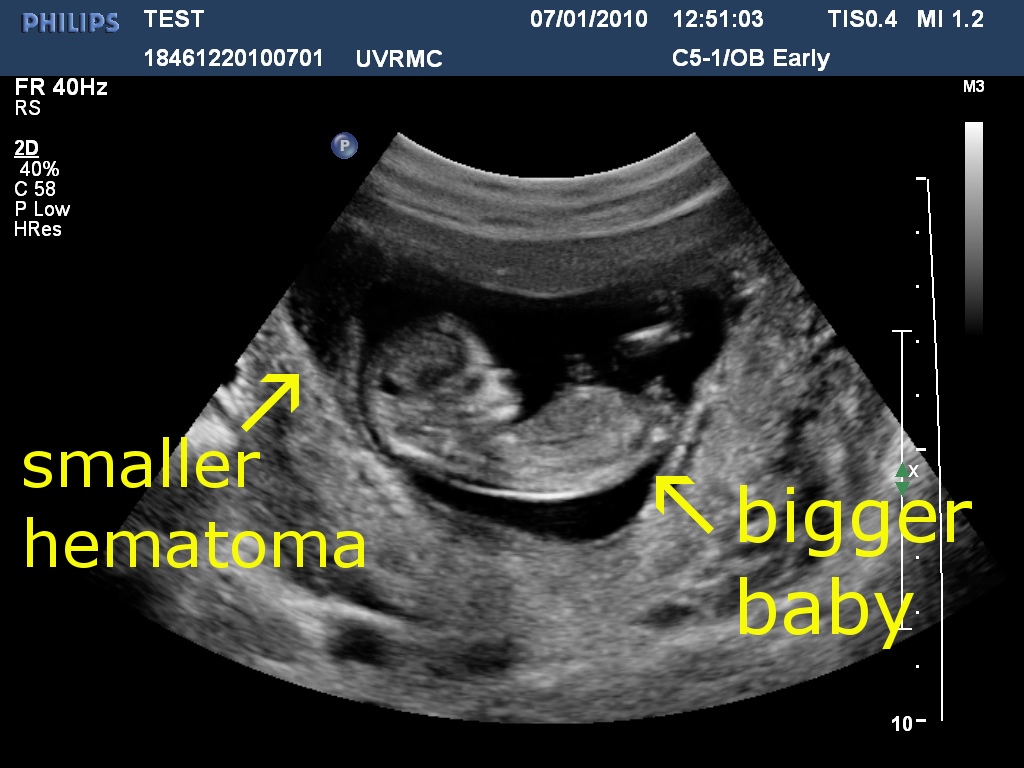

subchorionic hematoma weeks bleeding spotting sch continued another before